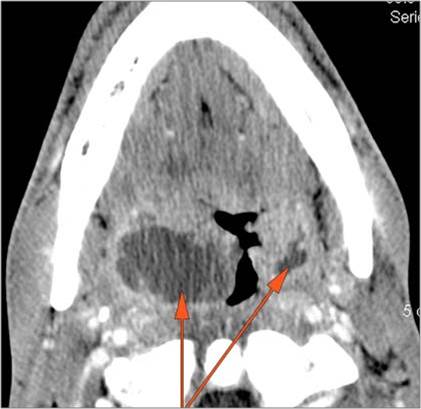

There is abscess at the periphery of the lymphoid tissue of the palatine tonsil within the potential peritonsillar space.